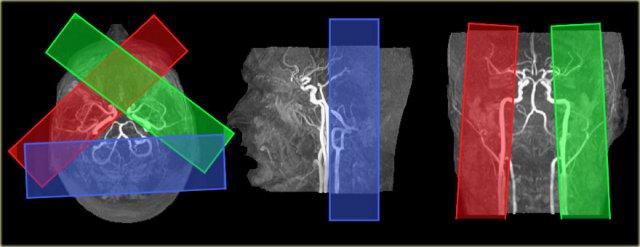

Các biến thể trong vùng tưới máu não có thể được hiển thị bằng kỹ thuật gán nhãn spin động mạch chọn lọc (selective arterial spin-labeling) (9).

Khả năng hiển thị các vùng tưới máu này có vai trò quan trọng trong các nhóm bệnh nhân đặc thù mắc bệnh lý mạch máu não, chẳng hạn như đột quỵ cấp tính, bệnh lý hẹp-tắc động mạch lớn và dị dạng động-tĩnh mạch, vì nó cung cấp thông tin huyết động học có giá trị.

Bên trái là hình ảnh chụp mạch máu MRI theo kỹ thuật thời gian bay (time-of-flight MR angiography) của các động mạch nuôi não, thể hiện kế hoạch lập các lát cắt chọn lọc để khảo sát vùng tưới máu của động mạch cảnh trong trái, phải và hệ động mạch đốt sống-nền.

Vùng tưới máu bình thường ở bệnh nhân nhồi máu ổ khuyết. Hình ảnh được cung cấp bởi Jeroen Hendrikse (9)

Bên trái là hình ảnh của một bệnh nhân có nhồi máu ổ khuyết bên trái với các vùng tưới máu bình thường.

Nhồi máu vỏ não thùy trán trái được tưới máu bởi động mạch cảnh trong phải. Hình ảnh được cung cấp bởi Jeroen Hendrikse (9)

Bên trái là hình ảnh của một bệnh nhân có nhồi máu vùng ranh giới (watershed infarct) ở bán cầu trái, đồng thời có nhồi máu vỏ não ở thùy trán trái (mũi tên).

Lưu ý rằng có sự biến thể trong tưới máu não, cụ thể thùy trán trái được tưới máu bởi động mạch cảnh trong phải.

Bên trái là một biến thể khác trong tưới máu não ở bệnh nhân có nhiều ổ nhồi máu được ghi nhận trên hình ảnh khuếch tán (diffusion imaging).

Có một ổ nhồi máu vỏ não nhỏ ở thùy chẩm trái, vùng này được tưới máu bởi động mạch cảnh trong trái (mũi tên).

Lưu ý rằng hệ động mạch đốt sống-nền không tham gia tưới máu cho vùng này.